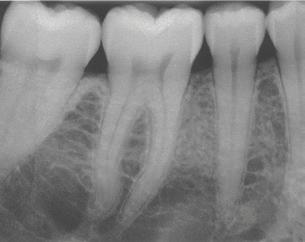

The culture of the hygiene program at Falcon Park Dental Group is proactive. We will quit watching and start treating. Our providers will link periodontal conditions to medical conditions and will refer to primary care physicians for unresolved inflammation. We will help our patients understand that bone loss is not a symptom; it is a RESULT. When we see bone loss on an x-ray, it is more destructive than it appears. We will also commit to using salivary diagnostics when indicated. We have committed ourselves to helping our patients understand that we must treat periodontal inflammation before it is too late.

Recognizing and treating periodontal disease in its earliest stages results in better patient outcomes and has been shown to positively affect the long term whole-body health of patients. Early disease recognition and management can only be accomplished by performing a thorough comprehensive exam which includes, but is not limited to, an oral cancer exam, full mouth pocket charting, and radiographs with a clear view of the interdental crestal bone. As clinicians, we know radiographic bone loss, no matter how minor, is a result of a long-standing infection in periodontal tissue.

Visually show bone loss through the patient’s own X-rays and/or the educational poster